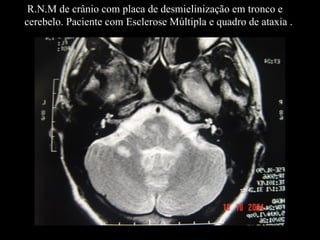

R.N.M de crânio com placa de desmielinização em tronco e cerebelo. Paciente com Esclerose Múltipla e quadro de ataxia .

R.N.M de crâniocom placa de desmielinização em tronco e cerebelo. Paciente com Esclerose Múltipla e quadro de ataxia .